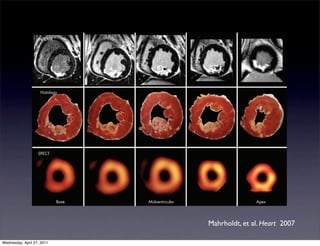

Histology

SPECT

Base                                                   Midventricular                                                 Apex

Figure 2 Contrast enhanced cardiovascular magnetic resonance (CeCMR), histology and single photon emission computed tomography (SPECT) images

obtained in an animal with a medium sized infarct. There is a nearly perfect match between necrosis defined by histology and ceCMR. Whereas ceCMR

Mahrholdt, et al. Heart 2007

allows the exact assessment of the transmural extent of infarction, SPECT defines segments as either viable or non-viable. Reproduced with permission from

Wagner et al.9